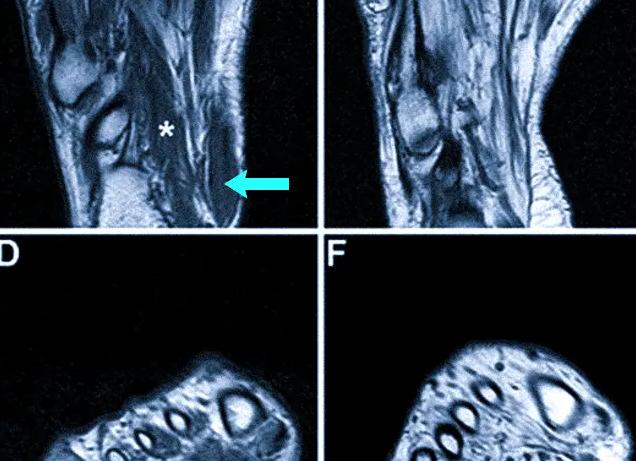

МРТ тонкого и толстого кишечника. Гидро МРТ. Колоноскопия

Существует множество эффективных и достоверных методов выявления патологий желудочно-кишечного тракта. Самыми информативными считаются гидро МРТ, колоноскопия и ирригоскопия, о которых и пойдет речь.